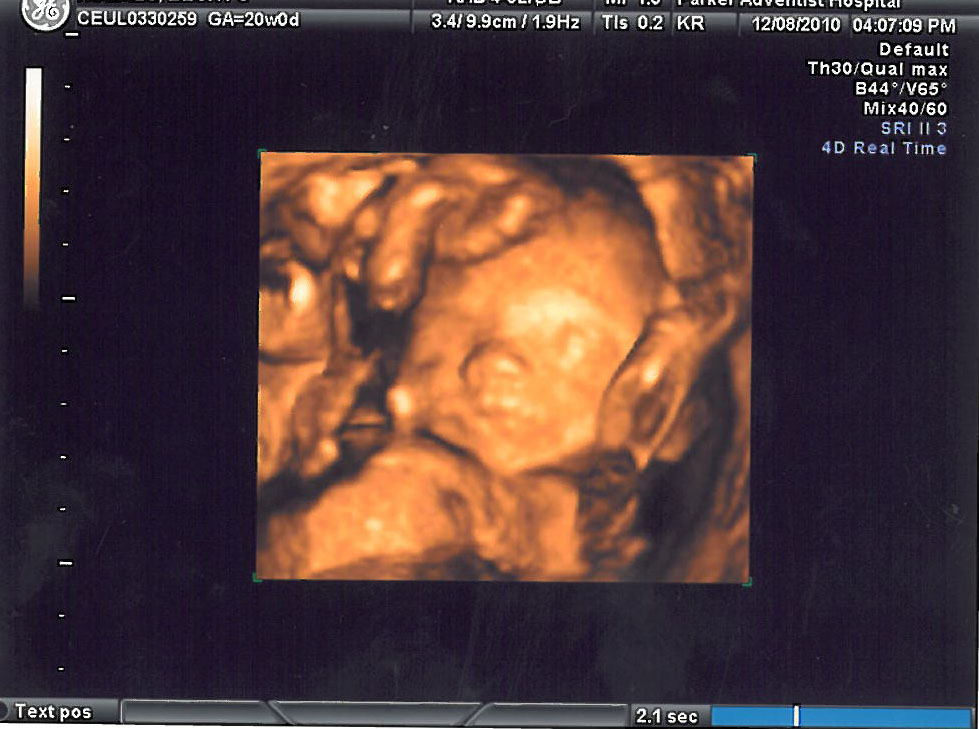

Had a 3D scan, which was magical, but I did think that her eyes seemed rather far apart at 20 weeks (but then that might just be unborn babies, I wouldn't know :p )

Are they likely to move in closer, or are they where they should be? Or do they just look far apart because she isn't finished filling out yet?

[IMG][/img]1798429_10152018807112998_2089158124_n.jpg